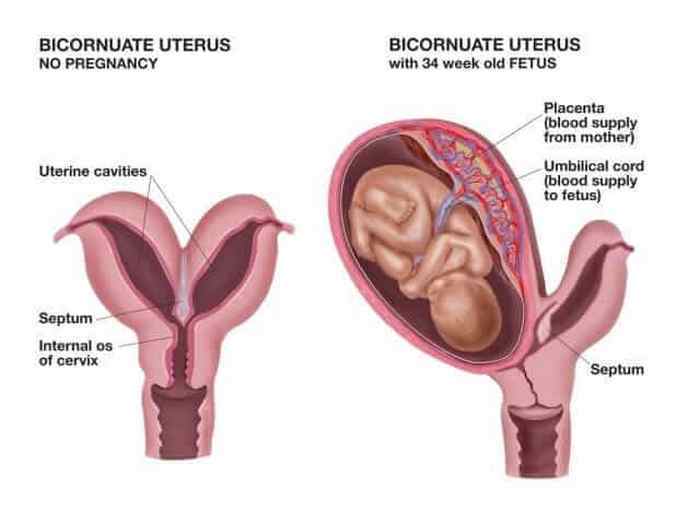

Сара Рейнфельдер

Большинство людей не знают, что эмбрион женского пола изначально имеет два одинаковых репродуктивных органа (например, пару матки и влагалища). По мере созревания эмбриона они сливаются в одно целое. Один из каждых 3 000 новорожденных рождается у женщины с патологическим состоянием "две матки". В будущем это может помешать нормальной беременности, вызвать тазовые боли и выкидыш. Одна из двух маток часто недоразвита или функционирует неправильно - в случае Сары, диагноз которой был поставлен в 2009 году, обе матки функционировали нормально. Затем она зачала близнецов, которые развивались в каждой матке. Дети родились здоровыми и без каких-либо отклонений.